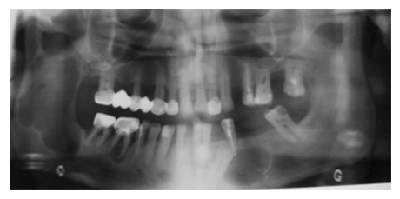

Рис.1. Ортопантомограмма пациента С. до лечения

Пациент С. 49л. поступил в отделение челюстно-лицевой хирургии мед. центра «Канакер-Зейтун» 30.03.2009г. с жалобами на онемение нижней губы и подбородка справа в течение последних 3-4 мес. Обращался к стоматологу по поводу плановой санации полости рта, и на ортопантомограмме, сделанной в стом. клинике, были обнаружены ки-стозные образования в области тела и ветви нижней челюсти. Пациент был направлен на стационарное обследование и лечение. При внешнем осмотре асимметрии лица не отмечалось. Кожные покровы в цвете не изменены, открывание рта свободное. Со стороны полости рта видимых патологических изменений не наблюдалось. На ортопантомограмме визуализировалось просветление в области угла и ветви нижней челюсти с четкими полицикличными контурами, окруженная склеротическим ободком. Неоднородность оттенков просветления создавало картину многокамерности кистозного образования. С левой стороны в области тела нижней челюсти прослеживалось кистозное образование с более четкими контурами, округлой формы и однородностью. Размеры кистозной полости справа около 7x5 см, слева около 4.5 см в диаметре (рис. 1).